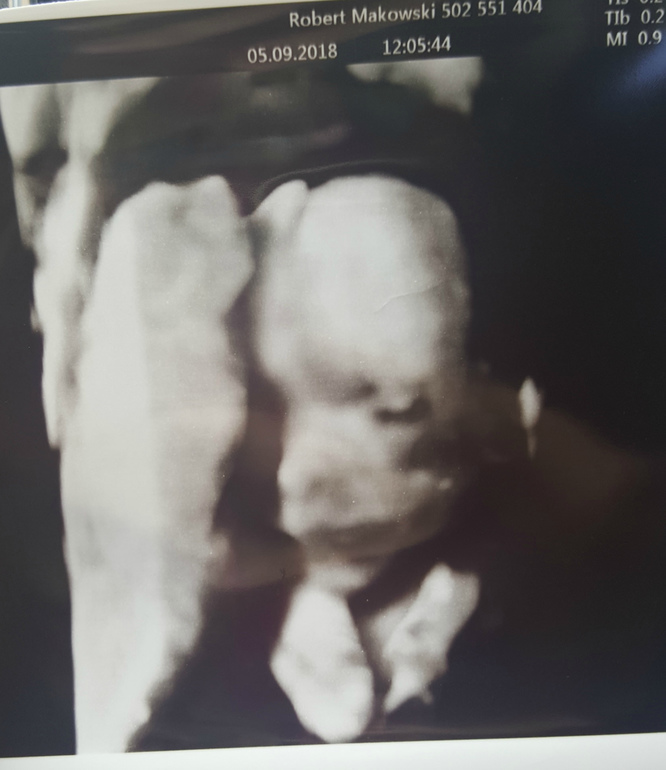

Были мы на УЗи 2го триместра, самое главное малыш здоров и развивается по сроку!!!

Срок 21 нед 2 дня

БПР= 48 мм

ОГ=188 мм

ОЖ=170мм

ДБ=35мм

Вес 450 гр, рост 25 см с ножками

носовая кость 7 мм

Органы все в порядке

ЧСС 140 уд/ мин

Очень меня тревожила тема определения и подтверждения пола нашего малыша и ура нам на 1000% подтвердили мальчугана!!!